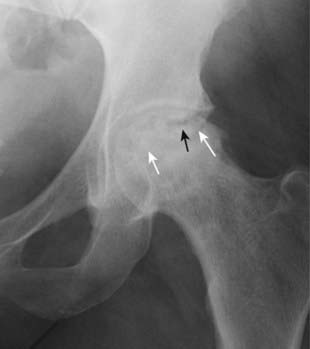

image

Figure 21-9 Avascular necrosis of the left femoral head in a patient on long-term steroids for lupus erythematosus.

A close-up view of the left femoral head shows a zone of increased sclerosis in the superior aspect of the femoral head (solid white arrows), a characteristic finding of avascular necrosis of the head. The linear, subcortical lucency (solid black arrow) represents subchondral fractures seen with this disease, called the crescent sign. Notice that the disease is isolated to the femoral head and involves neither the joint space nor the acetabulum, i.e., this it is not an arthritis.